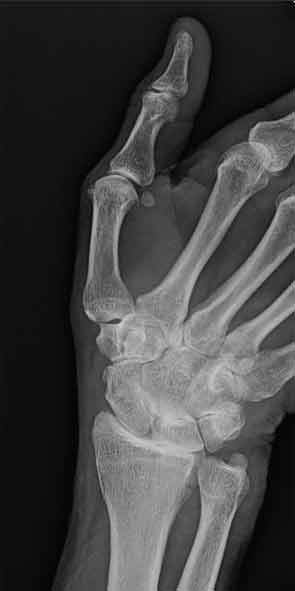

Bedside tool for diagnosing osteomyelitis in patients with diabetic foot ulcers. Several radiologic imaging techniques are used to diagnose osteomyelitis. Plain film x-rays are easy and relatively inex-pensive to perform. However, the infec- ... Retrieve Full Source